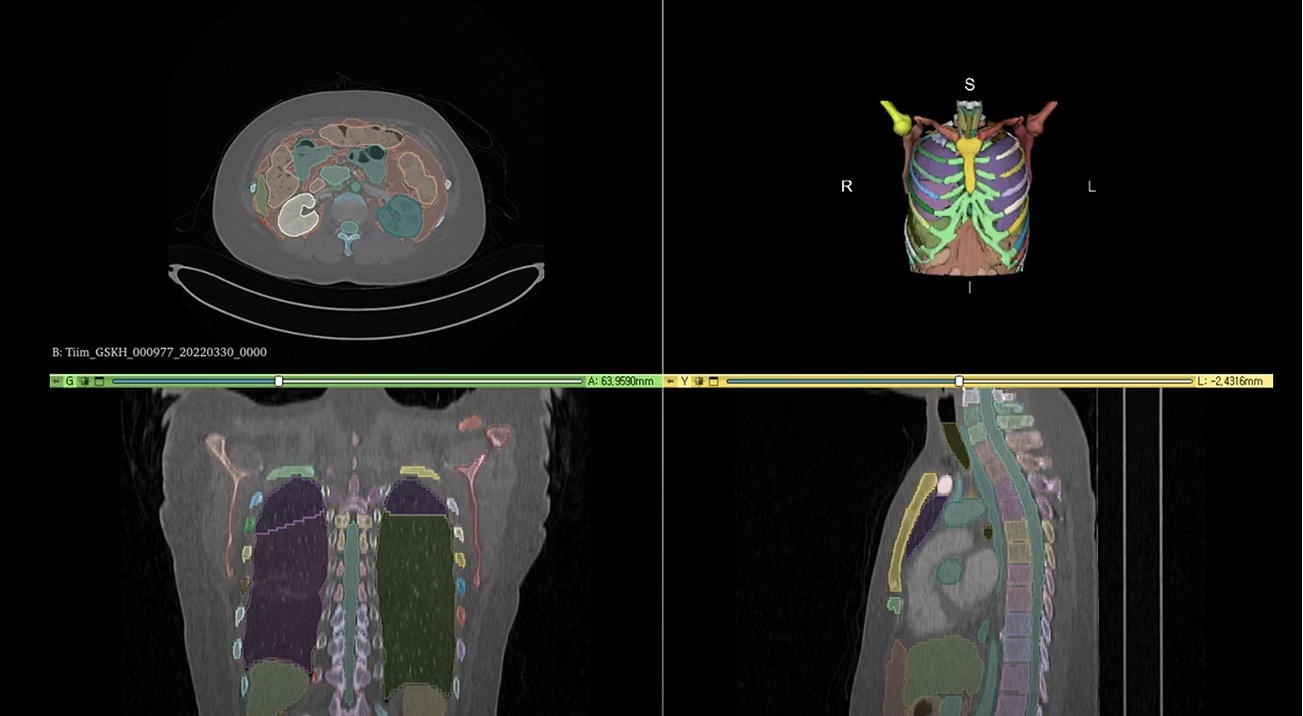

- 진단 자동화 지원 (RECIST & Segmentation)

폐암 진단 추적을 위한 RECIST 가이드라인 자동화 및 3D 디지털 트윈 솔루션과 연동하여, 의료진에게 데이터 기반의 직관적인 리포트를 제공합니다. - 의료 논문 키워드 자동 추출 및 분석

복잡한 유전체 분석 결과와 병리 슬라이드 데이터를 분석해 정밀 의료 시스템 구축을 지원합니다.